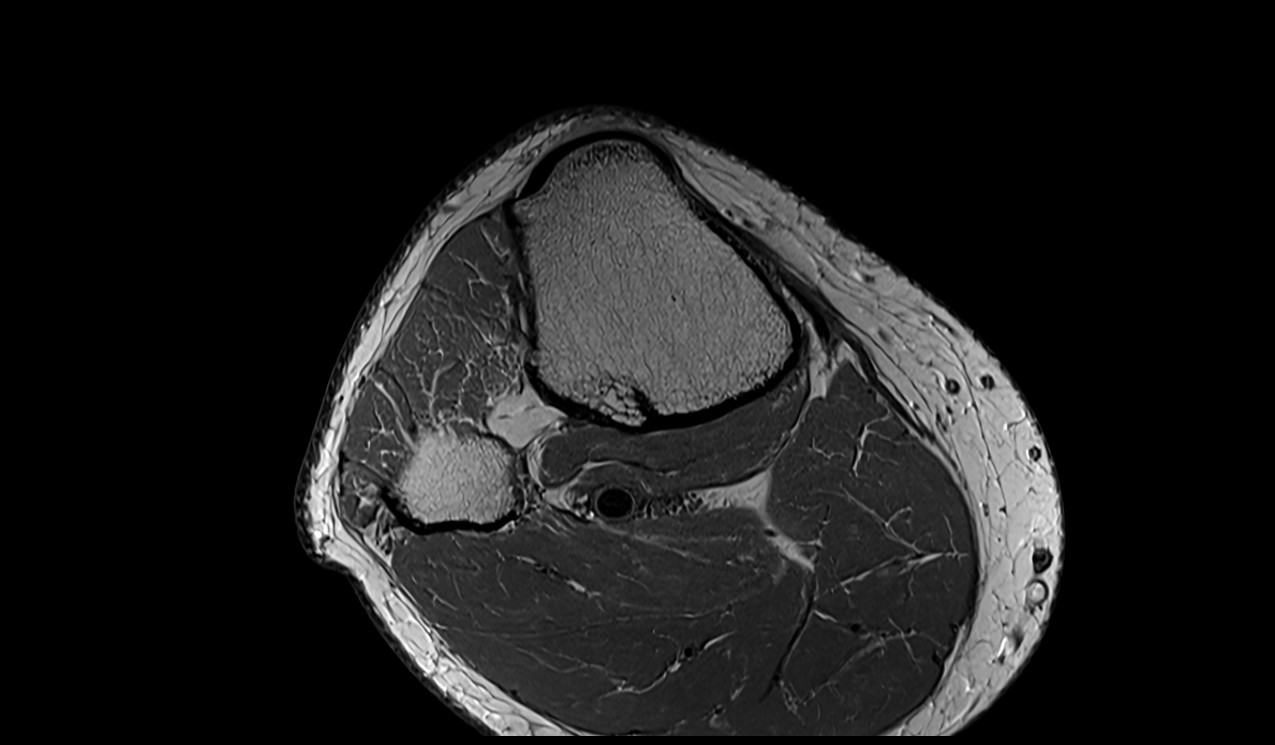

- Knee Joint

- Medial meniscus

- Lateral meniscus

- Patella